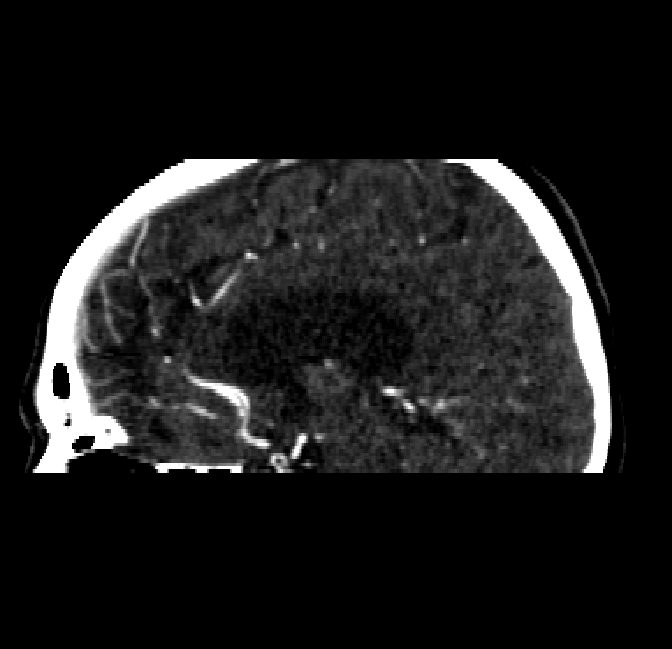

Refer to caption

Figure 4.8: Side view of segmentations on regions near the left side of the skull. Unaltered image (left). No pretrain model (mid-left). Fine-tuned model (mid-right). Hand-labeled ground truth (right).

The models appear to have a hard time segmenting vessels close to the skull surface. The model trained exclusively on patient data appears to struggle far more for these types on conditions than the fine-tuned models. Figure 4.8 shows an example of the fine-tuneds model having close to no trouble segmenting vessels near the left side of the skull, while the baseline model suffers heavily from false negatives. To lesser degree, this effect can also be observed in the frontal lobe of Figure 4.9 In the other hand, Figure 4.7 presents an example of both models failing to segment vessels near the top of the skull.

In the other hand, it should be noted that fine-tuned models suffered from false positives more often than models with no pre-training. The fine-tuned models appeared to occasionally segment regions near the skull, which although similar in intensity to vessels, had no resemblance in terms of shape. Examples of this are seen in Figure 4.4 near the occipital bone and near the right temporal bone. Examples of oversegmentation were observed to happen commonly around the internal carotid arteries. This is likely due to the amount of contact surface between the artery and the surrounding bone. There was also a tendency for all model conditions to segment bone regions that were similar in shape to large vessels (Figures 4.3 and 4.4). Bone structures in such regions have similar pixel intensities to the arteries transporting contrast material, which could explain the source of confusion for a model.